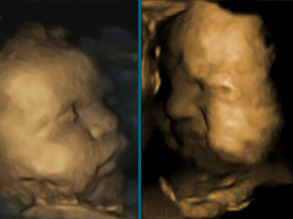

30

Baby Faces